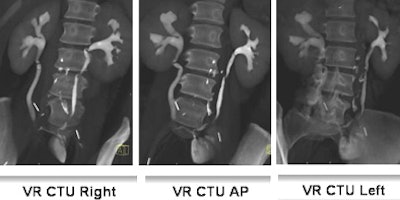

![]() |

| Fifty-three-year-old woman post cystectomy. Three VR CTU images (left to right: right oblique, AP, and left oblique) were created to depict the ileal neobladder reconstruction. Images courtesy of Dr. Terri Vrtiska, Mayo Clinic, Rochester, MN. |

The findings included medullary sponge kidney in three patients, UPJ obstruction in one, bladder transitional cell carcinoma in one, postoperative urinary tract reconstruction in two, upper tract indeterminate filling defect in two, and normal results in three patients. Two of three ureters that were not opacified in VR could be seen in either the prone or decompression scout views.